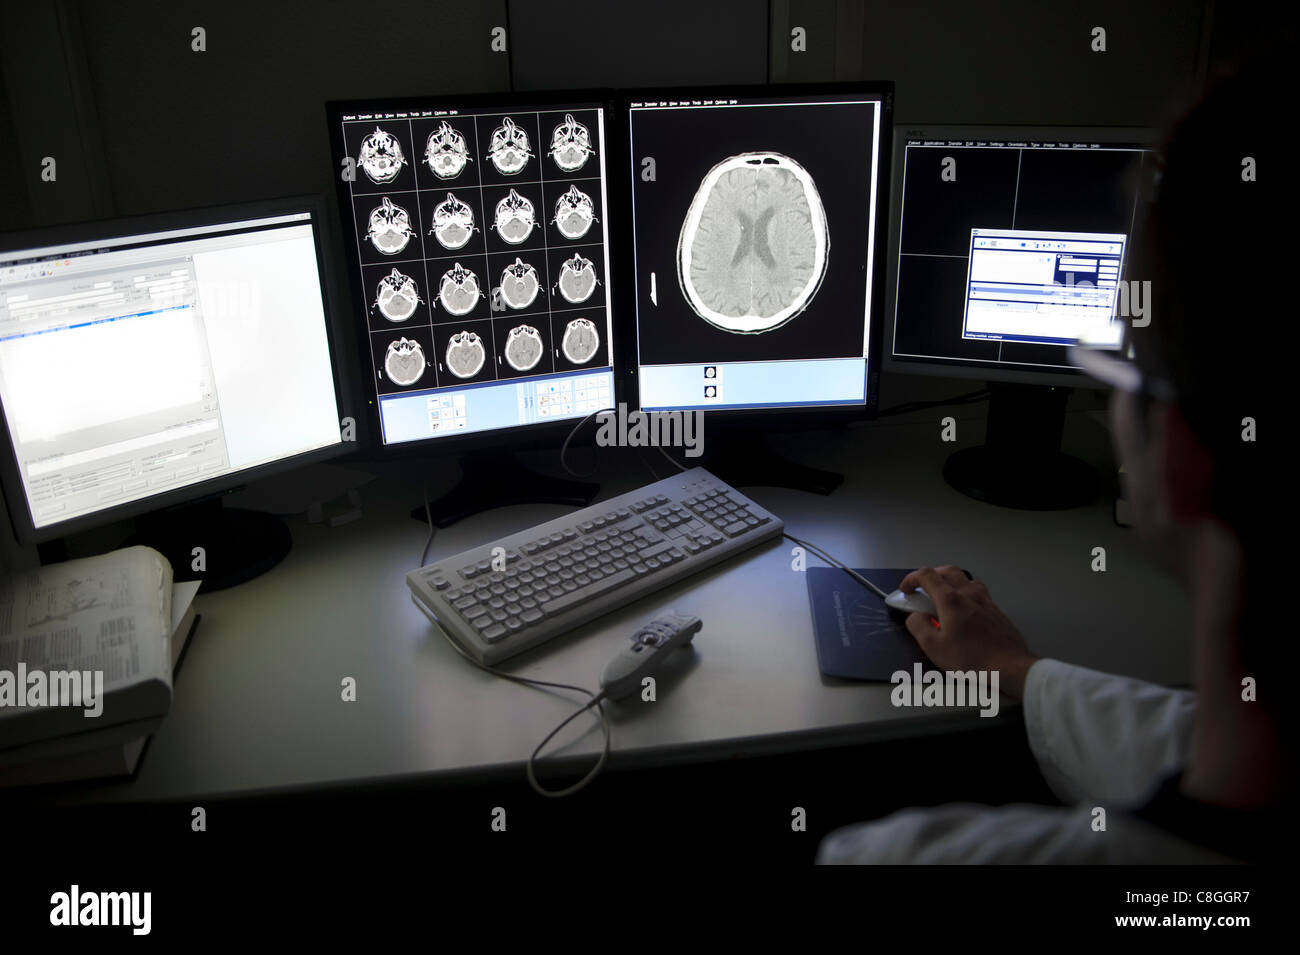

Doctor examining CT scan du cerveau à l'ordinateur Banque D'Imageshttps://www.alamyimages.fr/image-license-details/?v=1https://www.alamyimages.fr/photo-image-doctor-examining-ct-scan-du-cerveau-a-l-ordinateur-39702411.html

Doctor examining CT scan du cerveau à l'ordinateur Banque D'Imageshttps://www.alamyimages.fr/image-license-details/?v=1https://www.alamyimages.fr/photo-image-doctor-examining-ct-scan-du-cerveau-a-l-ordinateur-39702411.htmlRMC8GGR7–Doctor examining CT scan du cerveau à l'ordinateur

CT scan cérébral sur les écrans d'ordinateur Banque D'Imageshttps://www.alamyimages.fr/image-license-details/?v=1https://www.alamyimages.fr/photo-image-ct-scan-cerebral-sur-les-ecrans-d-ordinateur-39702393.html

CT scan cérébral sur les écrans d'ordinateur Banque D'Imageshttps://www.alamyimages.fr/image-license-details/?v=1https://www.alamyimages.fr/photo-image-ct-scan-cerebral-sur-les-ecrans-d-ordinateur-39702393.htmlRMC8GGPH–CT scan cérébral sur les écrans d'ordinateur